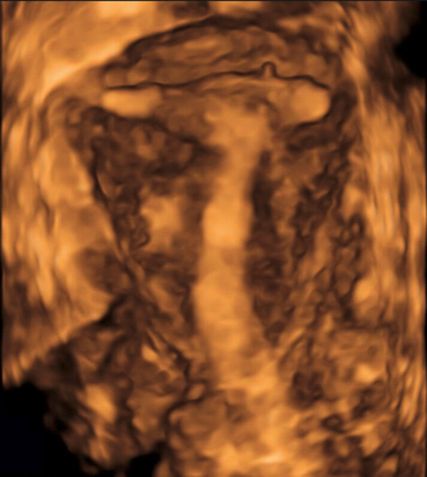

Die Untersuchung wird idealerweise bei hoch aufgebautem Endometrium durchgeführt. Nach Erstellung der Koronarebene kann sowohl die äussere als auch die innere Uteruskontur dargestellt und die Fundusdicke («fundal thickness», FTH) bestimmt werden (Abb. 2). Eine allfällige Septierung ist dabei einfach erkennbar und mittels eines Messkreuzes leicht objektivierbar. Dies lässt sich einfach konstruieren: Zunächst wird eine Hilfslinie zwischen den beiden inneren Tubenostien eingezeichnet (sog. Interostiallinie). Nun kann kranial davon die Fundusdicke (bis zur Serosa) und kaudal davon die Länge des Septums sowie der Winkel der Septumspitze bzw. Carina ausgemessen werden (Abb. 3). Je nach Klassifikationssystem unterscheiden sich hier die Definitionen bzw. Massangaben, welche zur Diagnose einer Fehlbildung nötig sind. Während die ESHRE-ESGE-Guideline relativ «laxe» Kriterien vorschlägt, unter deren Anwendung viele Patientinnen die Diagnose eines Uterus (sub-)septus erhalten würden (bis zu 80%!), landen gemäss ASRM-Klassifikation viele Patientinnen in einer «Grauzone». Hier bewähren sich die CUME-Kriterien, mit deren Hilfe eine Einteilung gelingt, die am ehesten der tatsächlichen Prävalenz entspricht, und dies bei entsprechender Trennschärfe.8 Die vorgeschlagenen Kriterien zur Diagnose eines Uterusseptums sind eine Septumlänge von mindestens 10 mm, ein Winkel von <140° und ein Verhältnis Septum:Fundusdicke von >110% (Abb. 4, Tab. 1).

Abb. 3: Ausmessen der Septumlänge. Nach Anlegen der Interostiallinie (grau) zwischen den Tubenostien können die Fundusdicke und das Septum (innere Einkerbung, engl. «indentation») ausgemessen werden. Nicht eingezeichnet ist hier die Messung des Septumwinkels

Dieselbe Gruppe publizierte Kriterien zur Diagnose eines T-förmigen Cavums, welches möglicherweise ebenfalls mit nachteiligen reproduktiven Outcomes vergesellschaftet ist.9